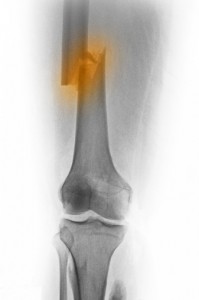

Supracondylar femur fractures are a less common type of femur fracture that affect the end of the femur located near the knee (see knee injuries for more details). This type of femur fracture is typically accompanied by damage to the cartilaginous surface of the knee joint. Supracondylar femur fractures are also commonly associated with the subsequent development of arthritis in the knee. All of this must be taken into consideration when determining the best treatment strategy.

Treatment for supracondylar femur fractures may include use of a cast or brace, use of an external fixator, or surgical insertion of plates, screws or rods to stabilize the bone and allow for healing.

This type of fracture is more common in patients with osteoporosis, a past knee replacement surgery, or those who have been injured in a high-energy accident.